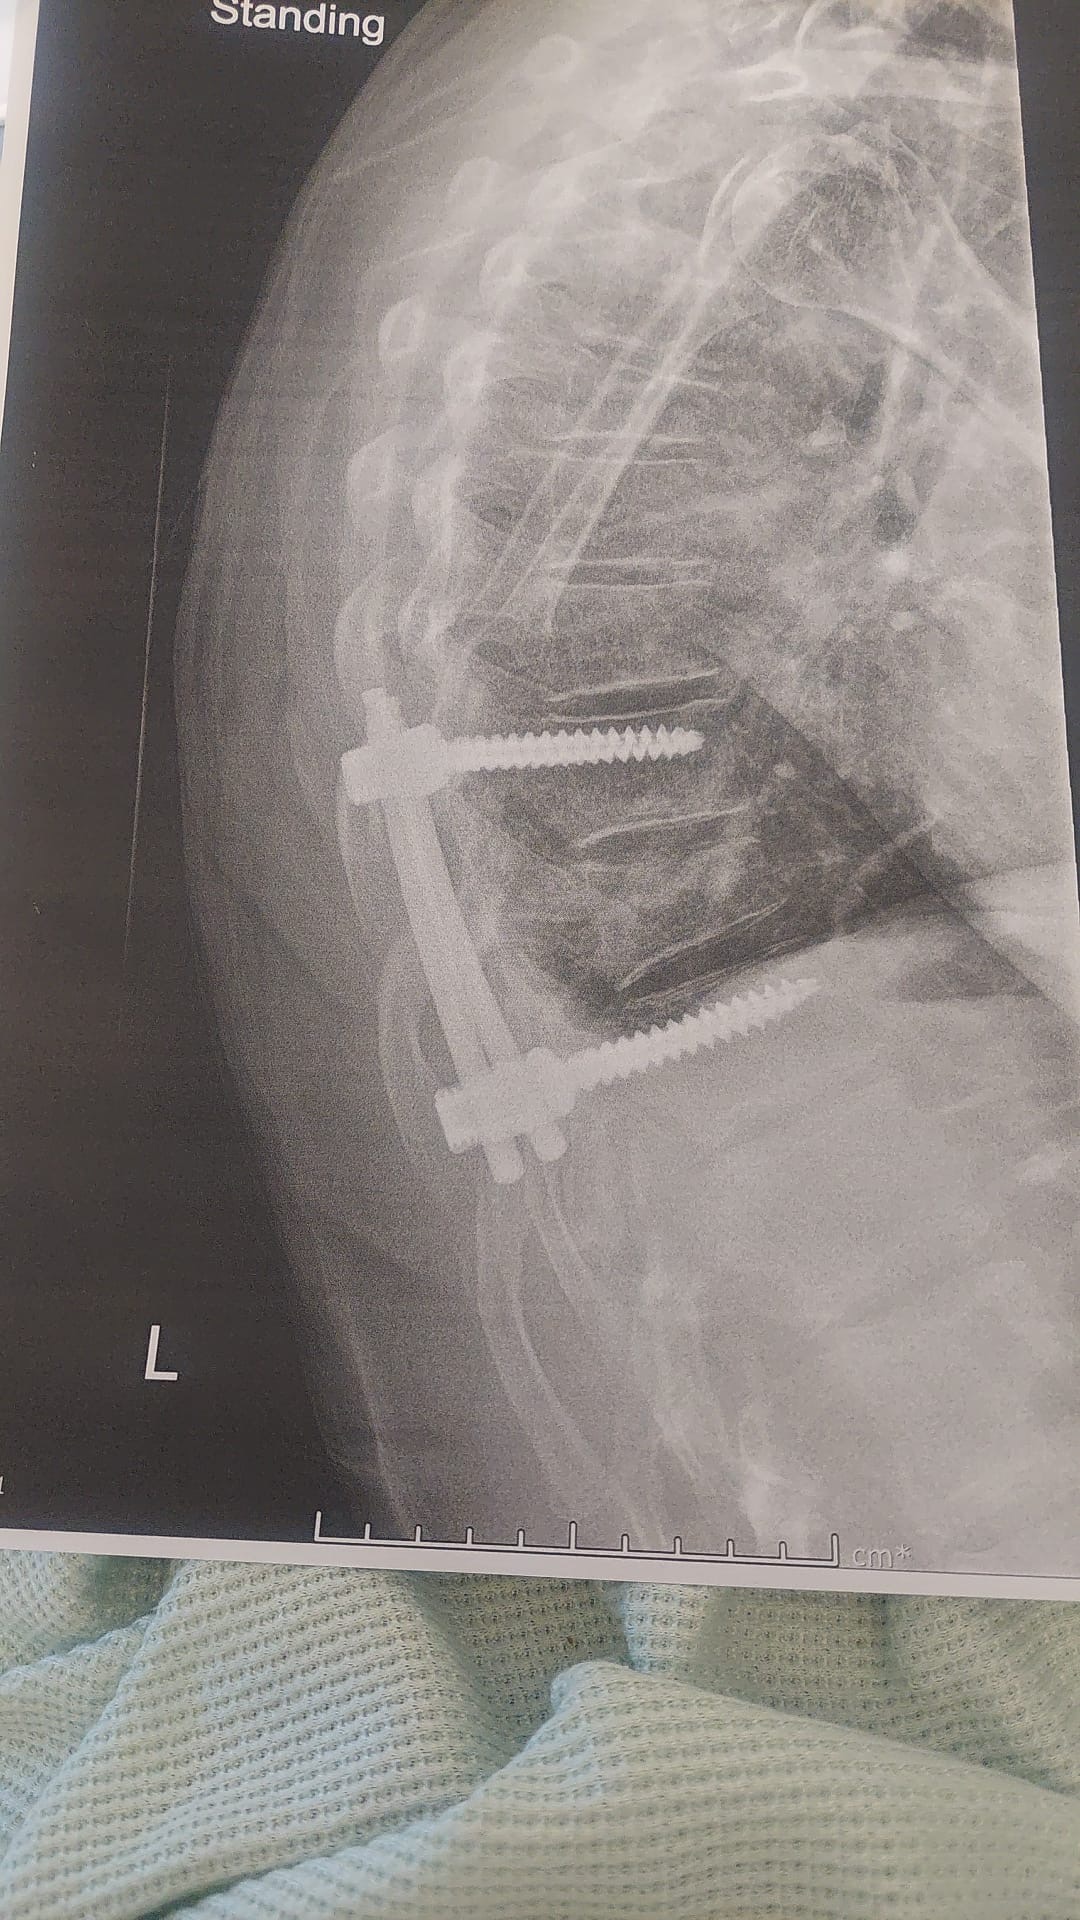

We’re reaching out to ask for your support for Jamie, a passionate and talented motorbike racer who recently suffered a crash at Snetterton Circuit at the 4th round of British Superbikes. Jamie fractured his back in three places which required surgery to make stable enough to ensure no neuromuscular issue. He has some numbness in his right arm but have been assured this will return in its own time. The surgery was successful but we all know the road ahead will be long and tough.